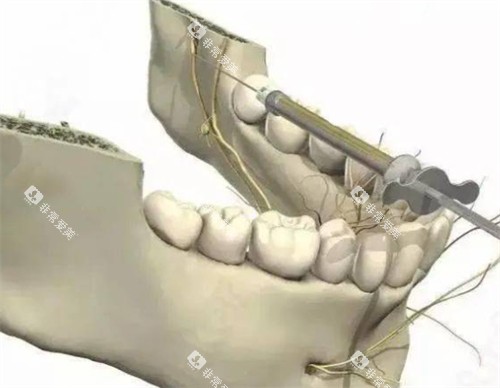

科室配备了一系列可靠的口腔诊疗设备,如智能化口腔全景机、种植牙系统、牙齿美白设备等,为患者提供各方位、高质量的口腔诊疗服务。

对于一些复杂的口腔手术,如种植牙、正畸治疗等,长治第二人民医院口腔科也有着较高的性价比。

在种植牙方面,科室引进了多种比较有名品牌的种植体,价格涵盖了不同的档次,患者可以根据自己的经济实力进行选择。

同时,医生娴熟的种植技术能够确保种植结果,大大提高了种植牙的成功几率。